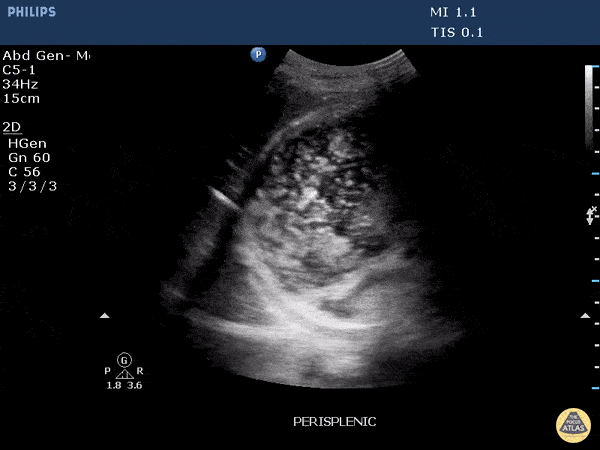

This clip demonstrates a full stomach. Gastric contents with internal air signatures can be seen swirling around within the stomach. Image courtesy of Robert Jones DO, FACEP @RJonesSonoEM Director, Emergency Ultrasound; MetroHealth Medical Center; Professor, Case Western Reserve Medical School, Cleveland, OH View his original post here